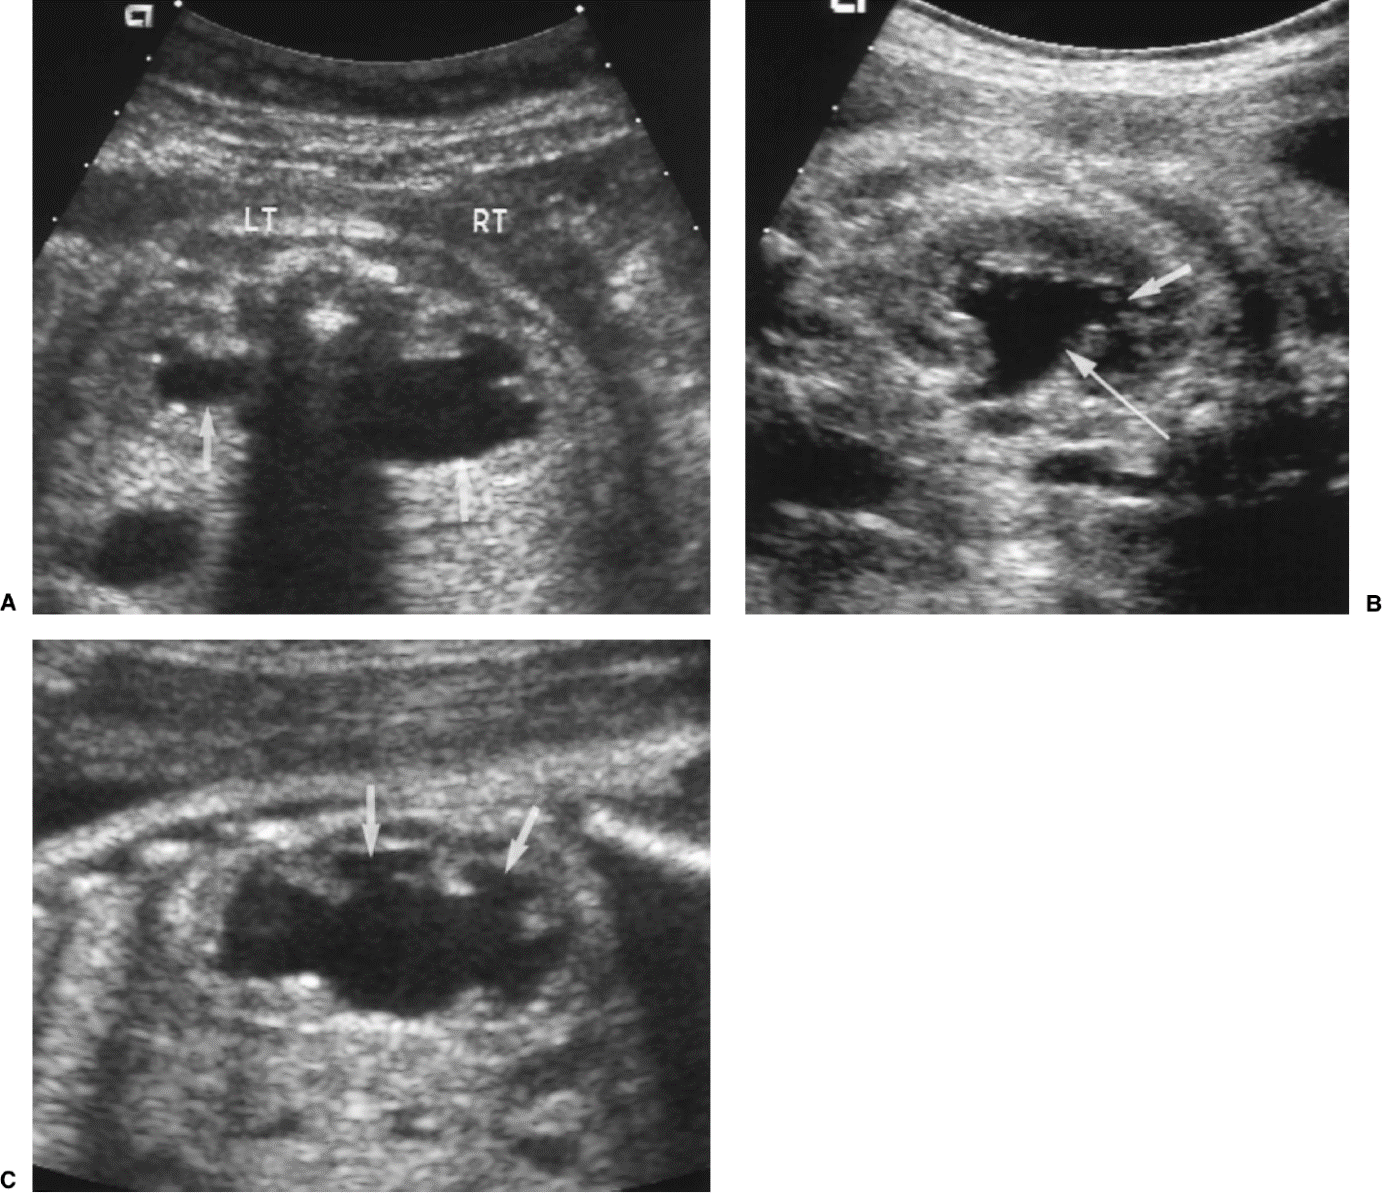

Links normale situatie: 1 nier, 2 nierbekken, 3 urineleider, 4 blaas, 5 overgang van urineleider in blaas, 6 plasbuis.

Rechts situatie zoals die bij urethrakleppen kan ontstaan: Verwijding van de nieren, het nierbekken en de urineleider. De urineleider wordt niet alleen wijder in de breedte maar ook in de lengte zodat en geslingerd verloop ontstaat. De blaas is zeer gespierd geworden en daardoor dikwandig en kartelig. De blaasuitgang is ook zeer gespierd en daardoor vernauwd. Het eerste deel van de plasbuis is verwijd tot aan de urethrakleppen. De blauwe pijl wijst naar de plaats van de urethrakleppen. Door de gespierde blaaswand wordt de urineleider die links in het plaatje zichtbaar is (dat is aan de rechter zijde van het kind) vernauwd waardoor de urineleider stroomopwaarts nóg meer verwijding vertoont. Aan de rechter zijde is de klep tussen urineleider en blaas beschadigd geraakt. De inmonding van de urineleider in de blaas is een wijde opening waardoor urine direct weer vanuit de blaas naar de nier kan stromen (Groene pijl)

20 weken echografie: links: dikwandige blaas met verwijding van de plasbuis tot aan de kleppen (pijl): het “sleutelgat teken”. Onder: verwijde urineleiders. Bij kinderen gaan de urineleiders bij verwijding ook erg gekronkeld verlopen.

Verwijde nierbekkens (lange pijl) en nierkelkjes (korte pijl). Smalle nierschors.